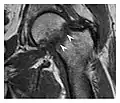

The greater tuberosity of the humerus is also an illustrative location of occult fractures. The osseous injury may follow seizures, glenohumeral dislocation, forced abduction, or direct impaction. They are commonly discovered on MRI in symptomatic patients with suspicion of rotator cuff tear. Coronal images are best suited for detection. They appear as crescentic oblique lines surrounded by a bone marrow edema pattern (Figure 5). The rotator cuff must be inspected since associated ligamentous lesions are common. In the ankle, malleoli and tarsal bones should be checked carefully for any cortical disruptions and radiolucent lines that may reveal a fracture. Awareness of the exact location of the pain will help direct the attention of the interpreter when searching for very subtle signs of fracture (Figure 6).[1]

a

b

Figure 6: Subtle anterior talar fracture in a 39-year-old man presenting with ankle pain after a fall. (a) Anteroposterior radiograph shows a subtle oblique radiolucent line through the talus (white arrows). (b) Sagittal CT reformation confirms the presence of an anterior talar fracture with cortical offset (black arrow). Avulsion fractures, which consist of a detached bone fragment resulting from a ligament or tendon pulling away from the bone, may also present with subtle radiographic signs. Tiny osseous fragments near the presumed attachment site of a ligament suggest this diagnosis. Common sites are the lateral tibial plateau (the Segond fracture), the spinal tuberosity of the tibia resulting from anterior cruciate ligament avulsion, and the ischial tuberosity.[1]